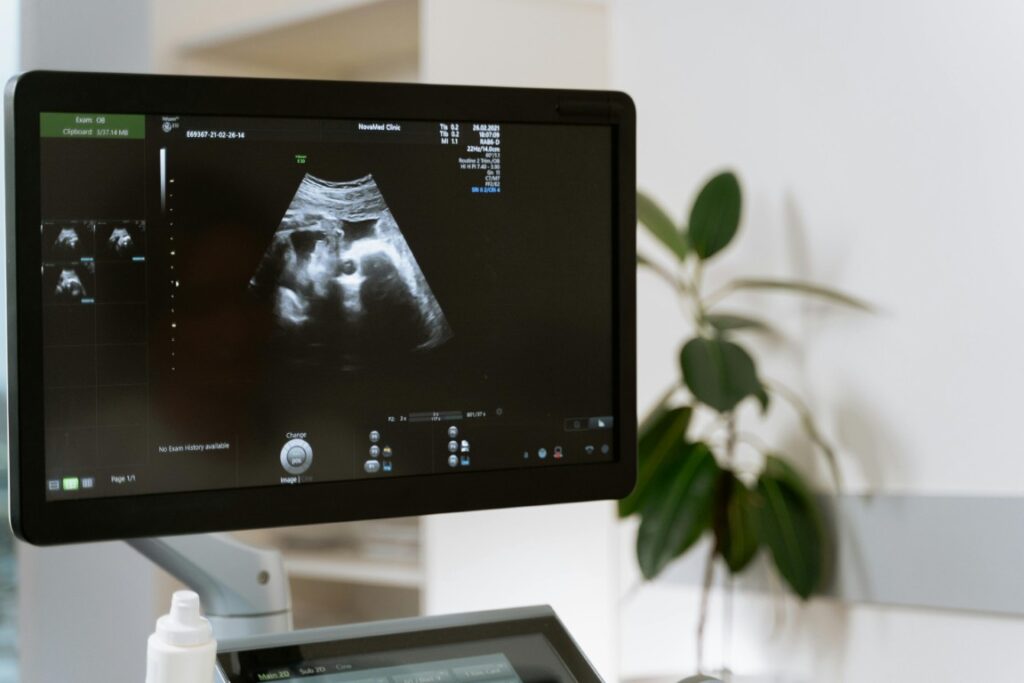

Esta semana es el momento de una de las pruebas más importantes y esperadas: la ecografía morfológica. En ella, nuestros especialistas revisarán minuciosamente toda la anatomía de tu bebé, órgano por órgano, para confirmar que todo se está desarrollando correctamente. Es una oportunidad única para verle con una claridad asombrosa.

Durante esta ecografía, si la posición lo permite, también podremos confirmarte el sexo de tu bebé, ya que sus genitales están completamente formados. Si es niño, sus testículos ya han comenzado a descender; si es niña, sus ovarios ya albergan los óvulos de toda su vida.